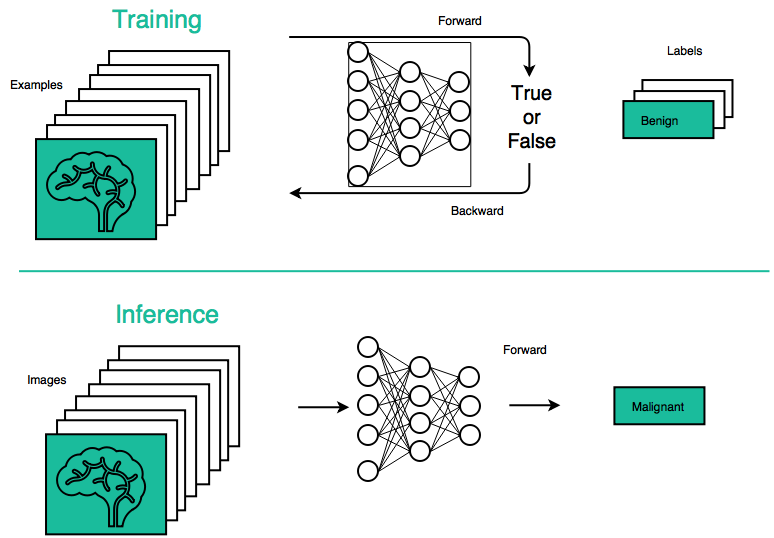

The advent of deep learning has revolutionized the field of computer vision and machine perception. On a high level, deep learning involves a two-stage process:

- A neural network is trained by tuning its numeric weights based on experience — in other words, determining its parameters using labeled examples of inputs and desired output. This makes neural nets adaptive to inputs and capable of learning.

- A network is deployed to run inferences, such as using its previously trained parameters to classify, recognize, and generally process unknown but similar inputs.

Behold.ai uses a class of artificial neural networks called Convolutional Neural Networks to identify abnormalities in medical images. Neural Networks are composed of neurons arranged in a series of layers. ConvNets are specialized for image processing tasks and are inspired by the biological visual cortex.